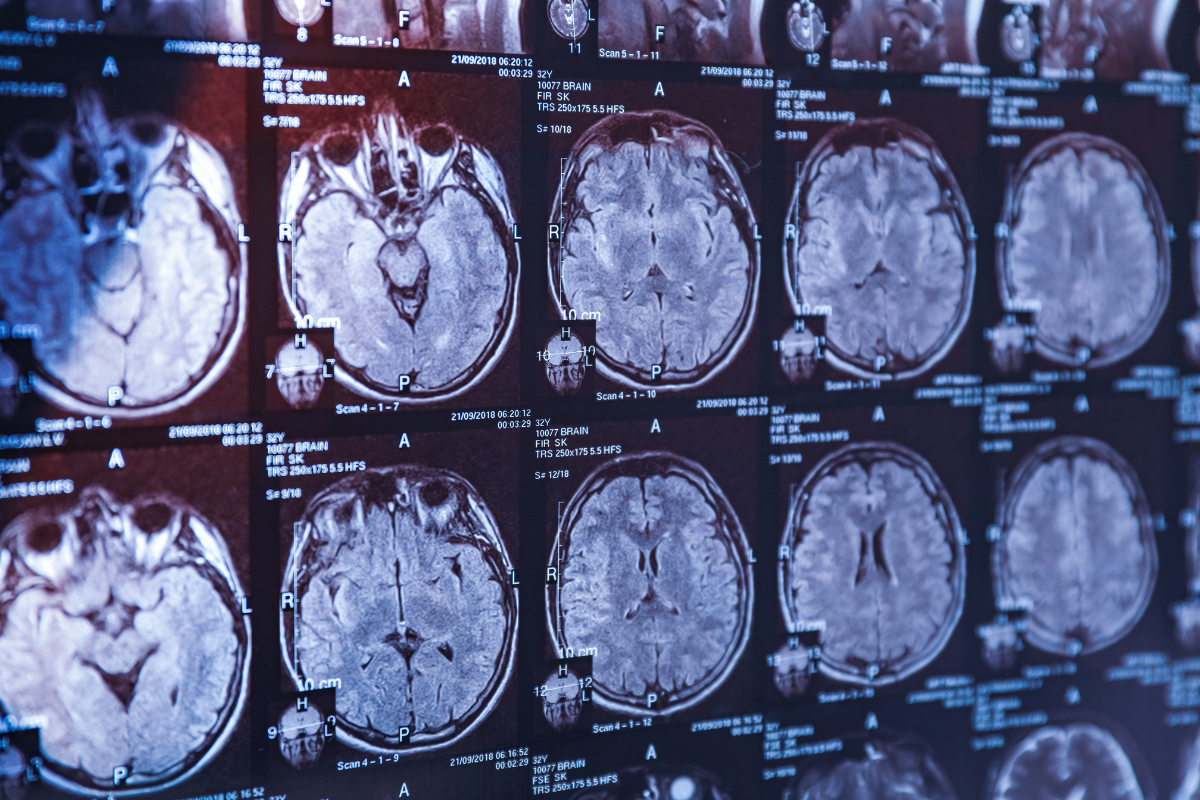

Vận động vừa phải giúp chậm suy giảm trí nhớ và giảm nguy cơ Alzheimer. Ảnh: Canva